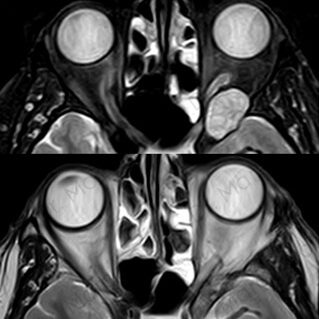

ÓRBITA

TUMORES ORBITARIOS